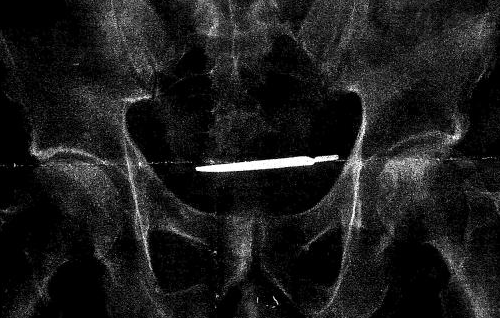

X光图(来源:CBS)

据CBS消息,来自美国康涅狄格州西南部城市的退伍军人格兰福特·特纳(Glenford Turner)上周在美国地区法院起诉了该医院。根据法庭文件,特纳于2013年在涅狄格州军人医院接受了手术。而将近4年后,他因眩晕和剧烈的腹痛返回医院。X光检查结果显示他的身体内有一个手术刀。为了去除这把手术刀,特纳不得不再次接受手术。